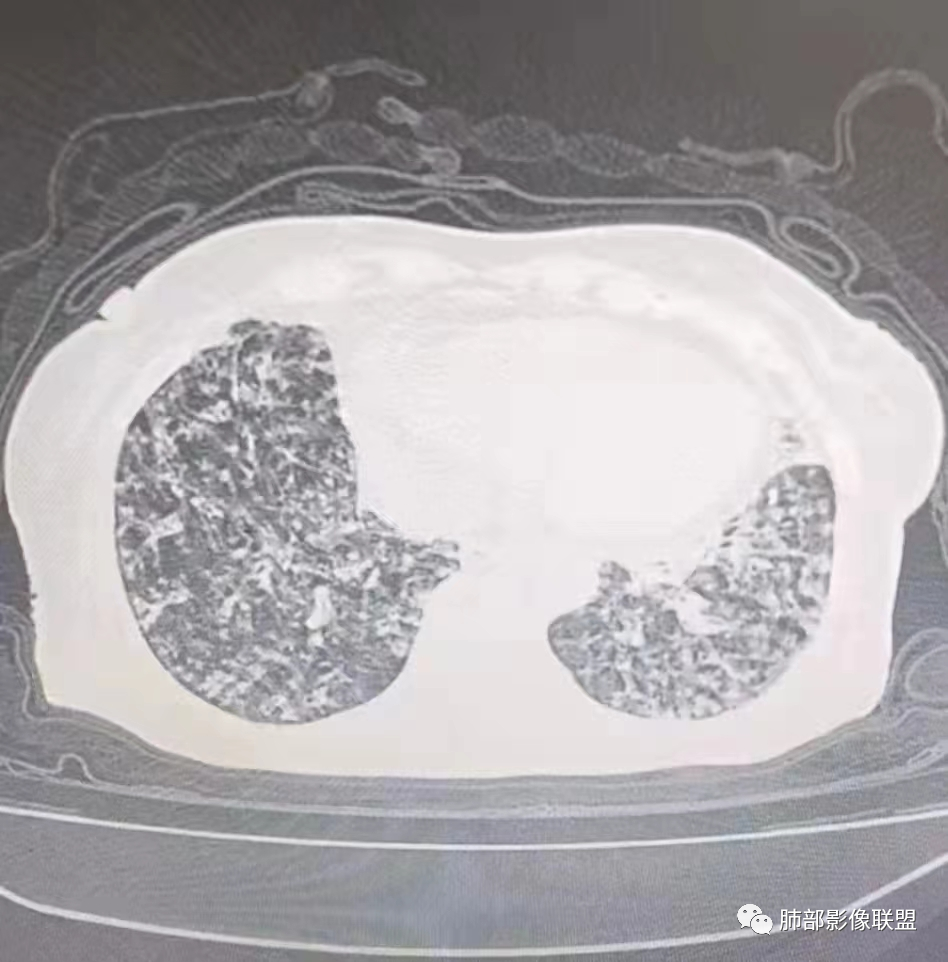

右肺中叶及左肺舌叶支气管扩张,双肺下叶斑片,小片状影伴磨玻璃影,边缘部分模糊。炎性指标不高,血糖略高,考虑支扩合并真菌感染。NTM。

男,21,咳嗽伴左胸壁痛2天。胸部CT:右中叶、左舌叶支气管扩张,双肺下叶斑片影,左下多发,沿支气管束分布,小片状影伴磨玻璃影,边缘模糊,树雾?考虑支扩合并感染,支原体?NTM?鉴别ABPA、CPAM、隔离等。

2、影像特点:右肺中叶、左肺下舌段可见支扩。左肺下舌段及两肺下叶可见片状实变影及发结节影,病灶边界多显示不清,纵隔窗显示病灶密度较均匀,未见液化、空洞或钙化。左肺下叶部分病灶沿支气管分布,并可见局部支气管管壁增厚。